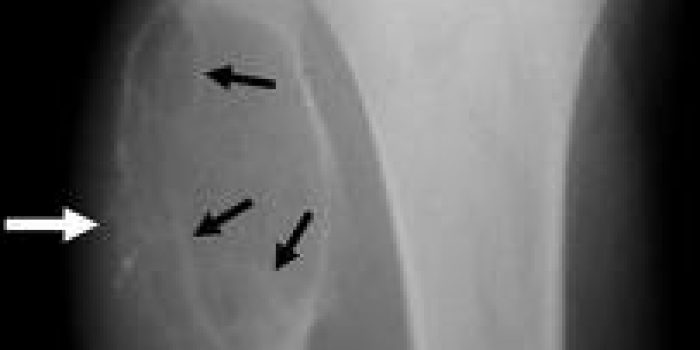

کیست آنوریسمی استخوان در رادیوگرافی بصورت یک حفره استخوانی دیده میشود که مانند یک بادکنک برجسته شده و معمولا دیواره های نازکی دارد. ام آر آی به تشخیص آن و افتراق آن از دیگر تومورها کمک میکند.